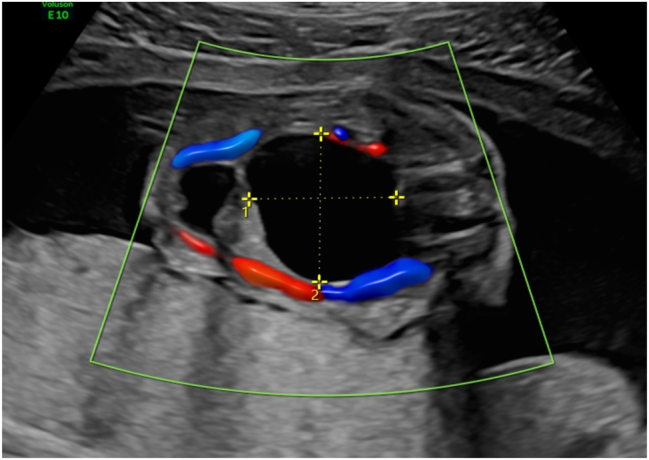

Case presentation: This is a unique case of a 29-year-old second gravida, suspected of having a fetal sacrococcygeal dysplasia differentiable between Type 2 SCT and terminal myelocystocele. An MRI revealed no typical SCT changes, as a matter of course, the diagnosis of myelocystocele could not have been excluded. The results of the genetic examination allowed to exclude the chromosomal pathology. Punctuation of the external component of the formation and a cytological examination were suggested. Nevertheless, the patient and her partner refused further studies and insisted on the termination of pregnancy. Medical abortion was induced and histological findings confirmed fetal morphology to be mature SCT.